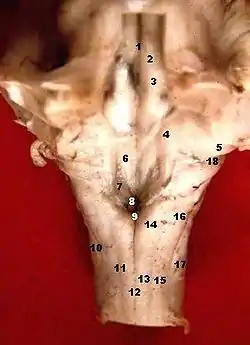

![]() Human caudal brainstem posterior view (Lateral aperture is #18) | |

The lateral aperture of the fourth ventricle or foramen of Luschka (after anatomist Hubert von Luschka)[1] is an opening at the lateral extremity of either lateral recess of the fourth ventricle opening anteriorly[2] into (sources differ) the pontine cistern[2]/lateral cerebellomedullary cistern[3] at cerebellopontine angle.[3] A tuft of choroid plexus commonly extends into the lateral aperture, partially obstructing CSF flow through this aperture.[4]

The opening of the lateral aperture occurs just lateral to the cranial nerve VIII,[2] and proximally to the flocculus of cerebellum.[4]